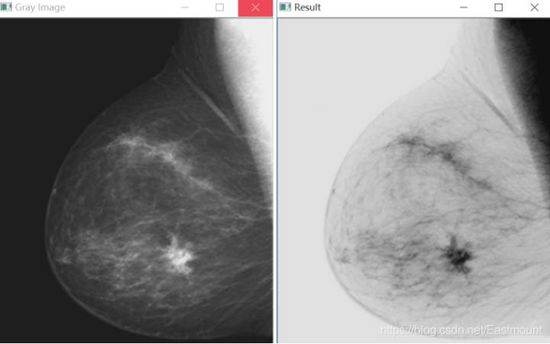

图像灰度反色变换在医学图像处理中有一定的应用,如下图所示: